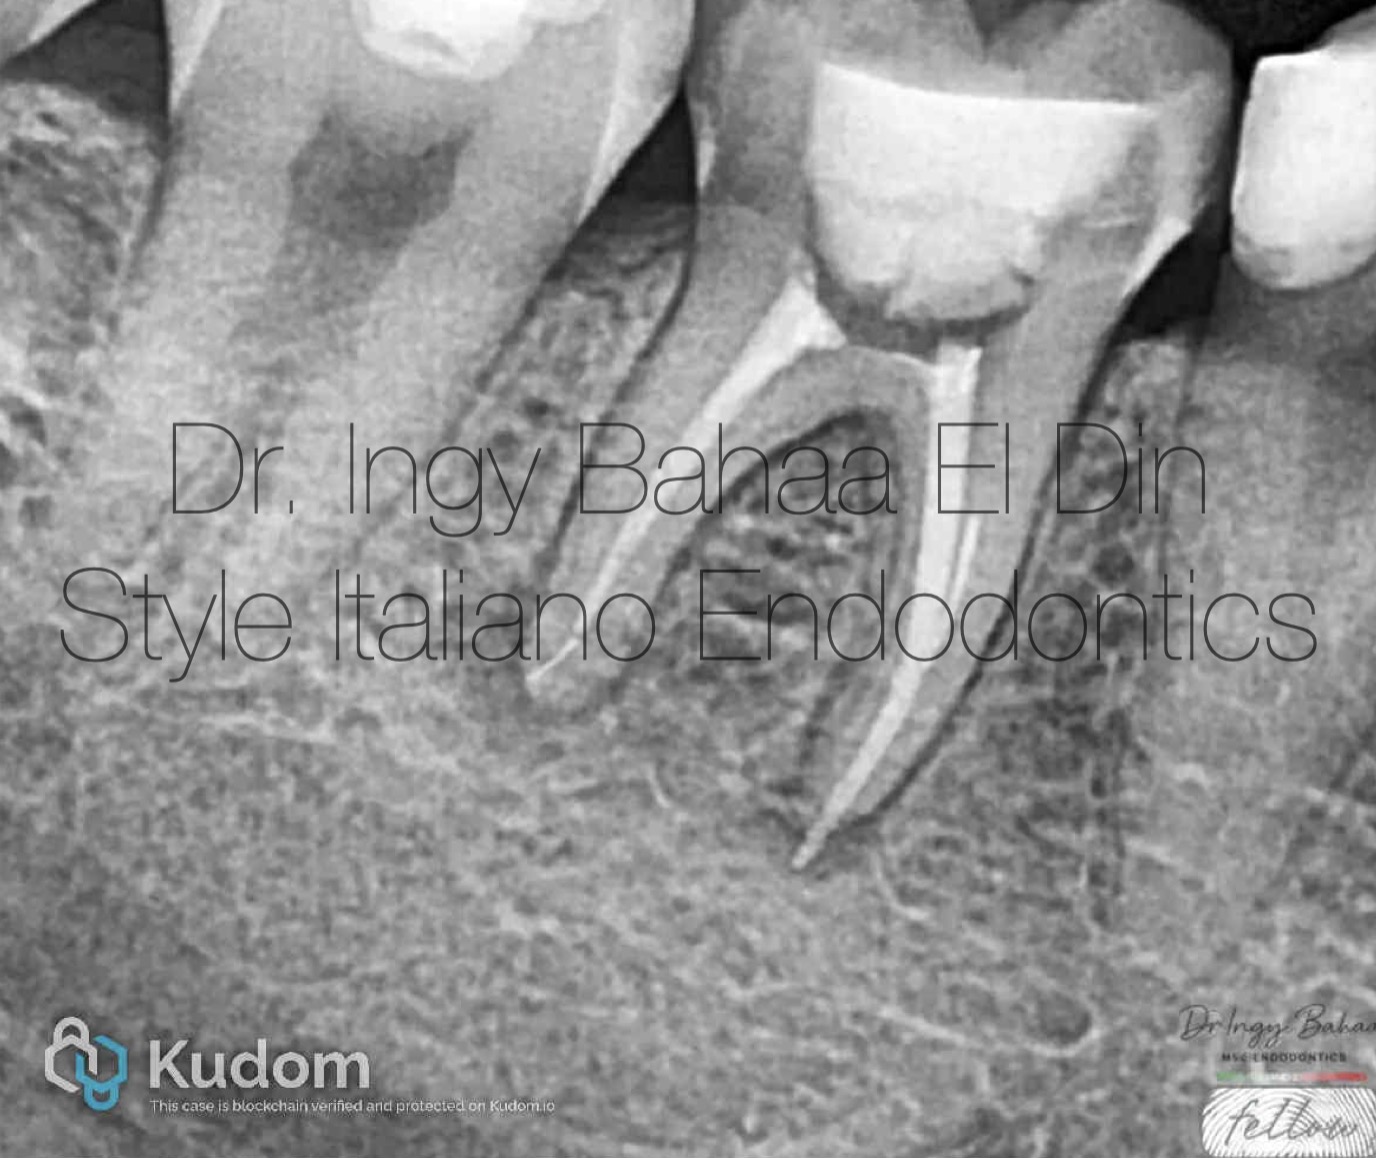

Fig. 3

Removal of old GP was done sequentially using Retreatment rotary files and copious irrigation using NAOCL 5.25% , after achieving success in removing all remnants we have a more clear vision of the broken files